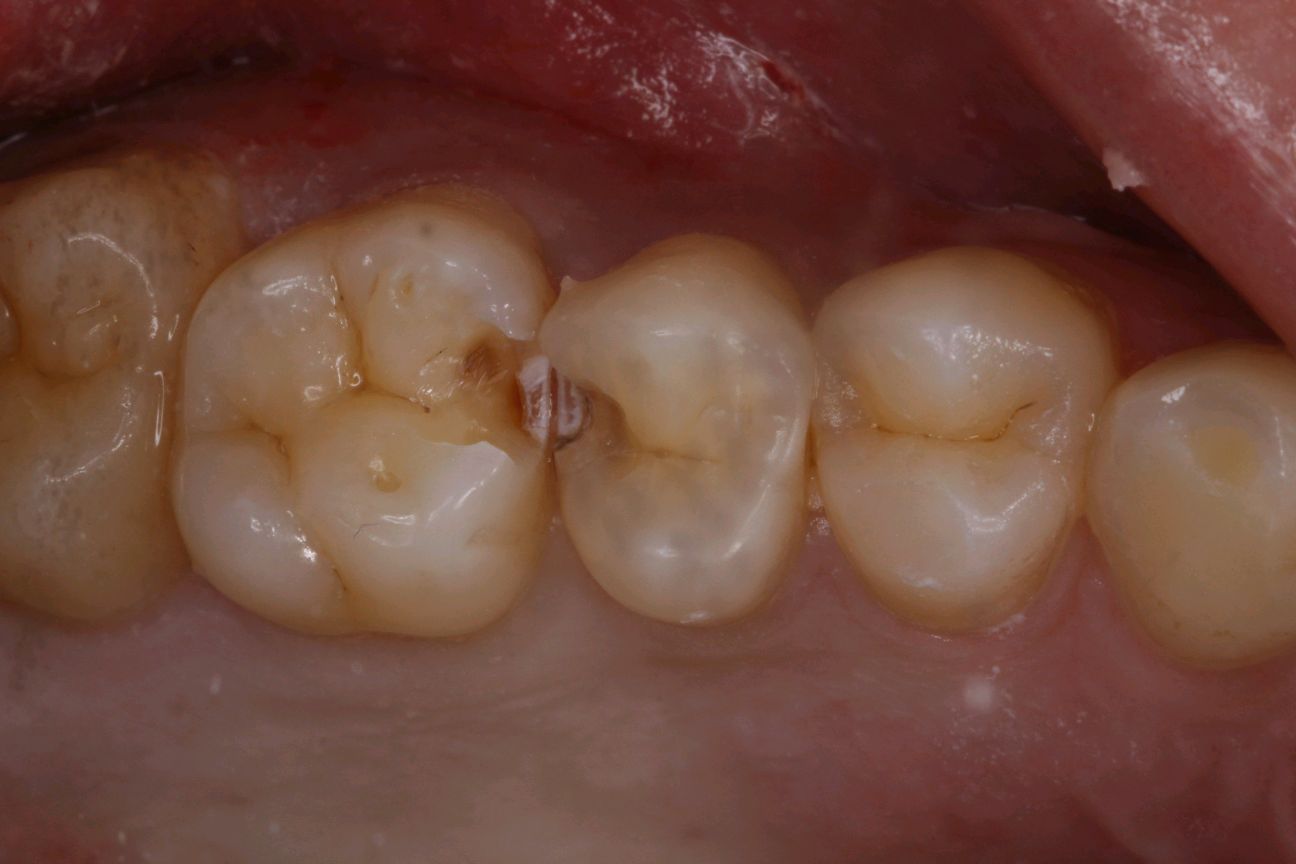

患者男,28岁。主诉左上后牙食物嵌塞。检查发现25、26邻面龋坏,色泽发黑,质硬 冷测正常,余无特殊。治疗计划:去腐后嵌体修复。

图片发自160App

术中